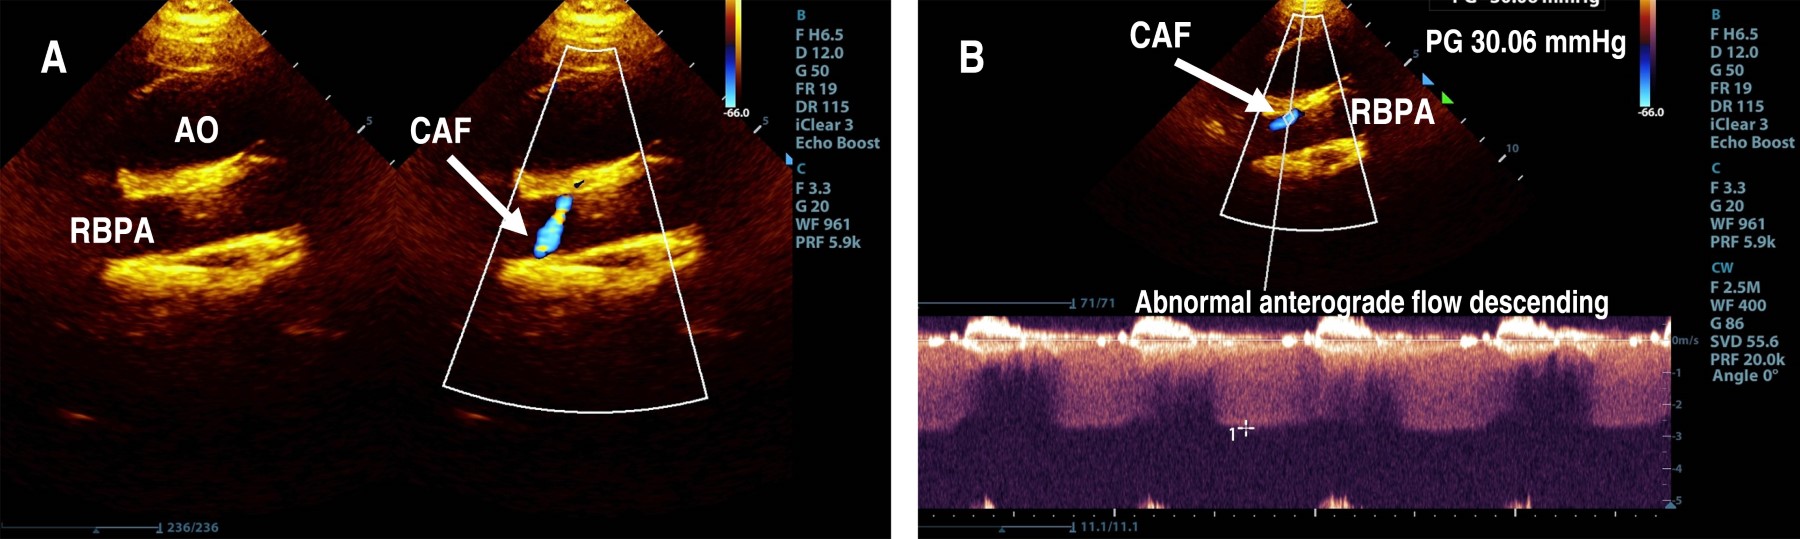

The parasternal short-axis view of the aortic root showed the right coronary artery (RCA) and left coronary artery (LCA) in their appropriate anatomical positions, with the proximal segment of the RCA exhibiting a Z score of 0.2 (Figure 1). However, the suprasternal longitudinal view identified an abnormal vascular structure with anterograde flow descending into the right branch of the pulmonary artery (RBPA) (Figure 2). The suprasternal short-axis view illustrated an anastomosis at the proximal segment of the RBPA, characterized by continuous, pulsatile flow, a maximum recorded velocity of 2.8 m/s, and a maximum gradient of 31 mmHg (Figure 3).